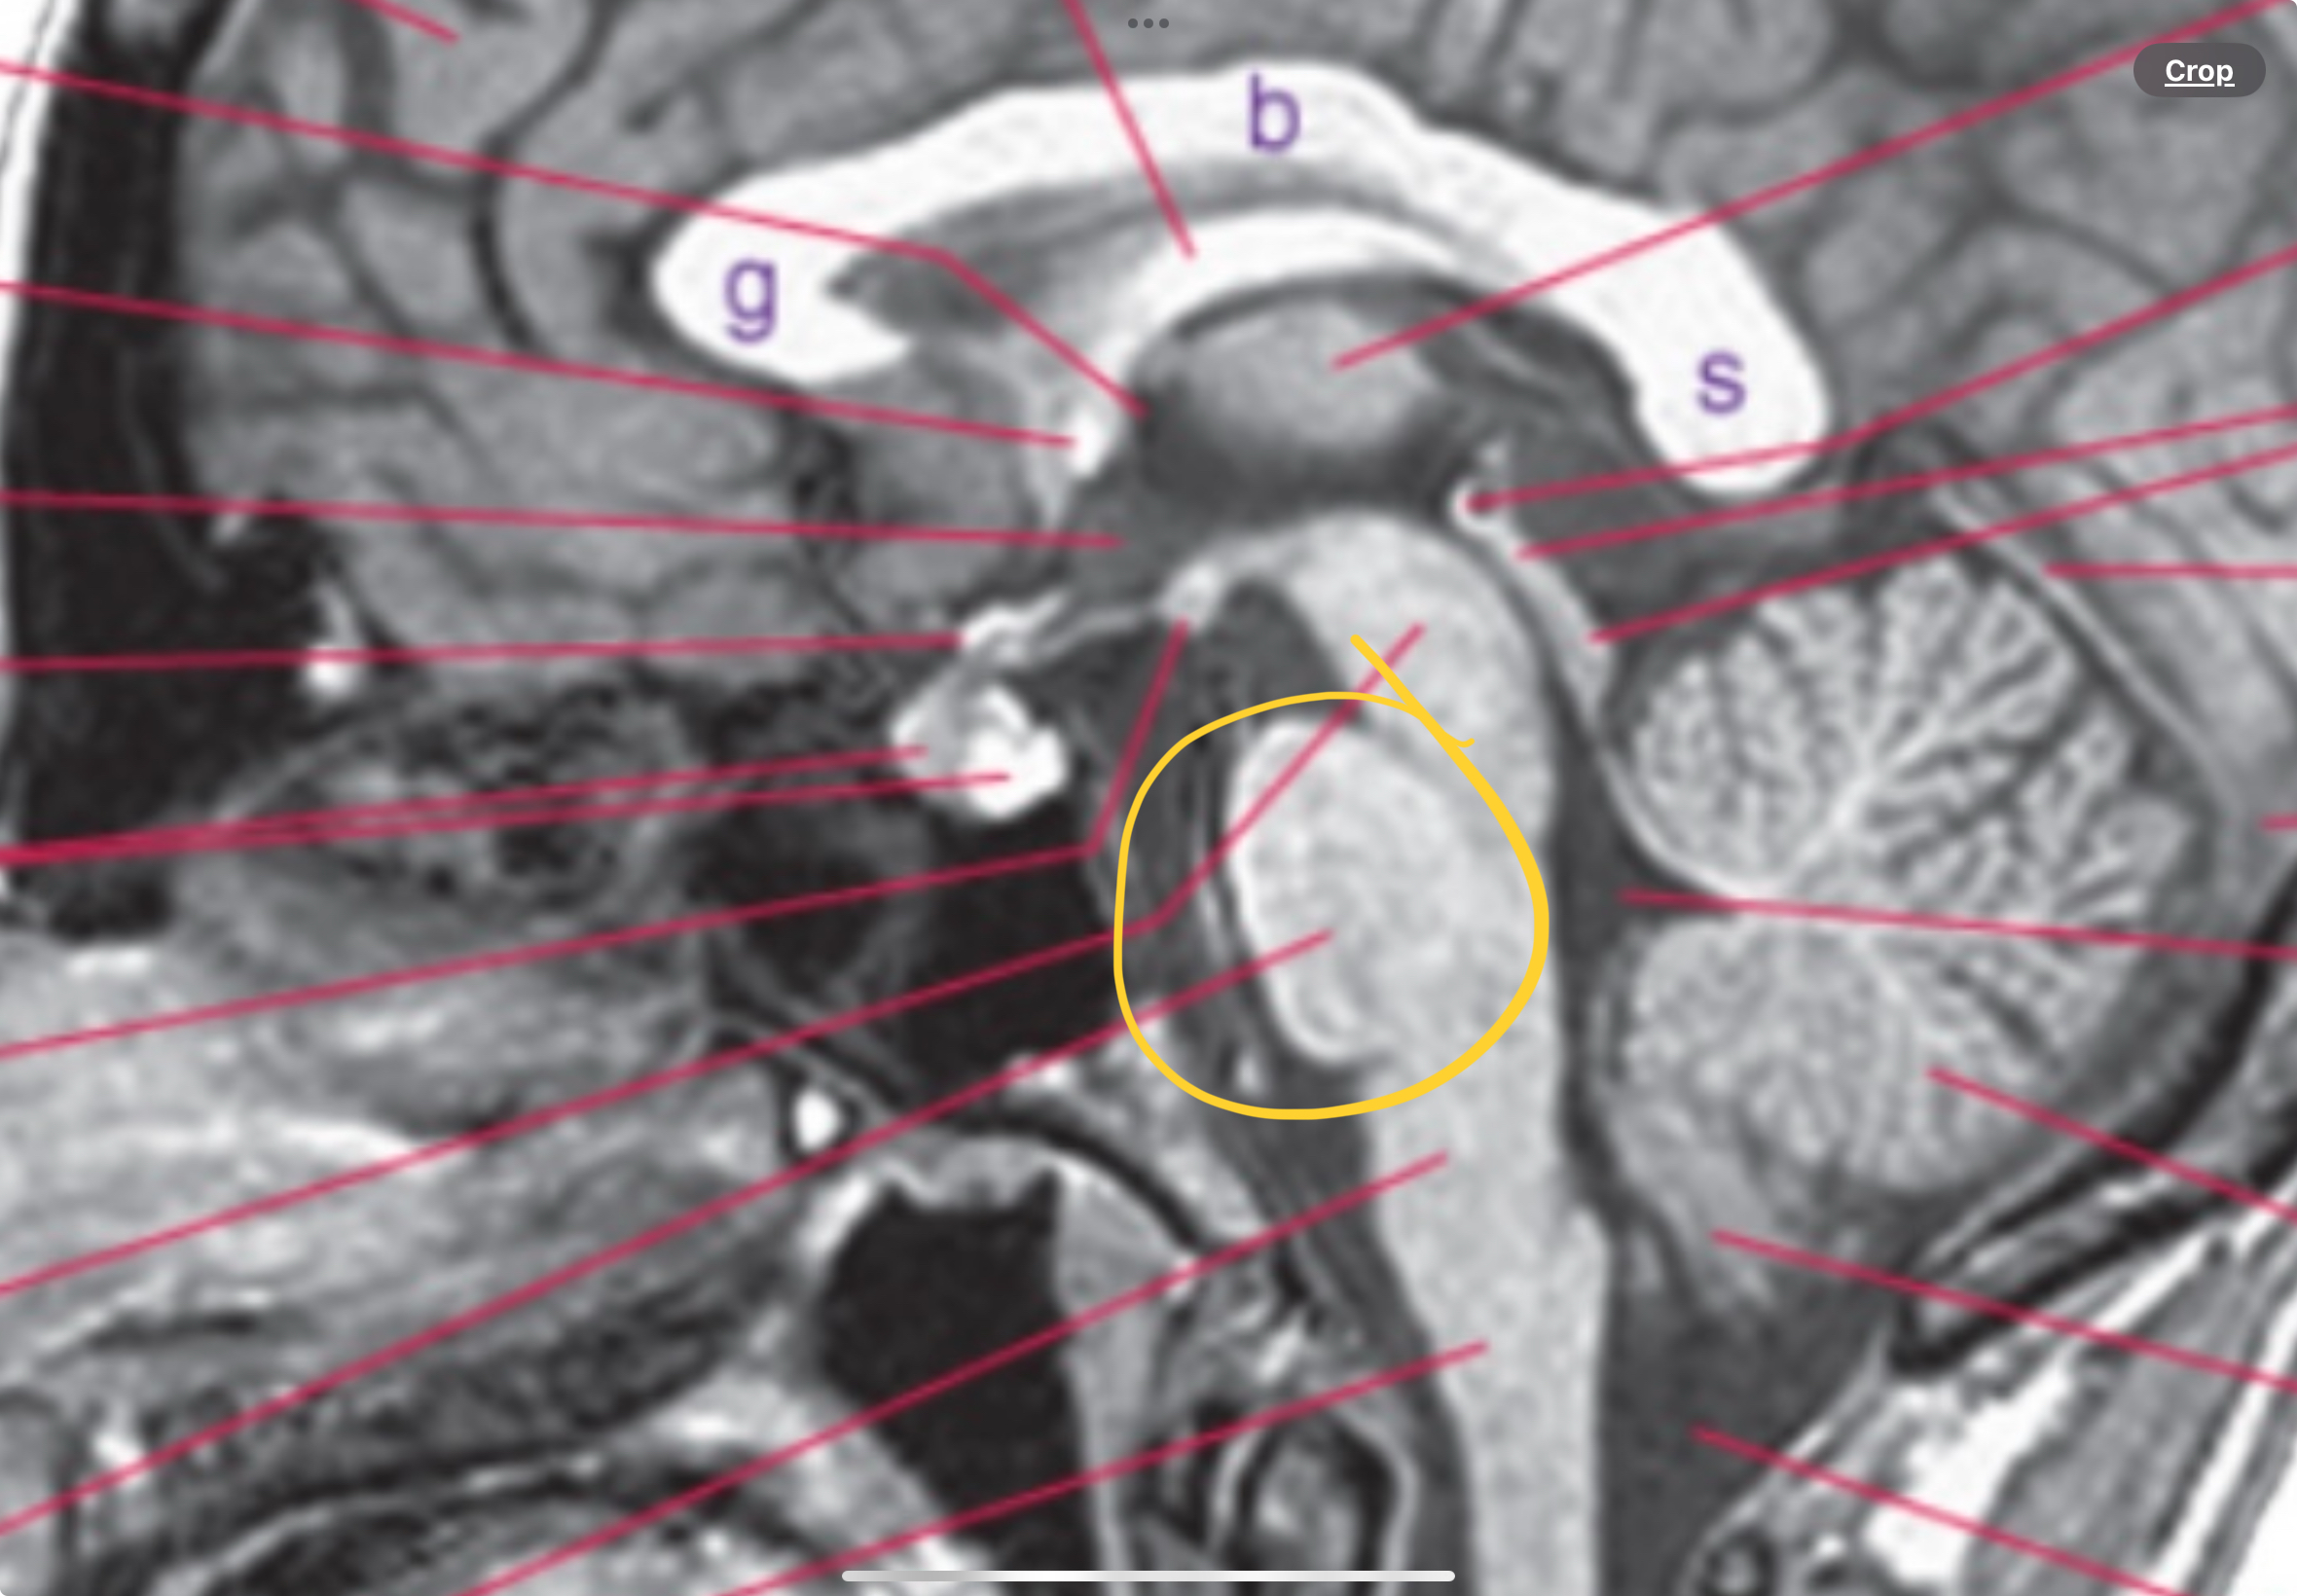

Includes cerebral penduncle, superior and inferior colliculus, and aqueduct

Cerebral penducle, superior/inferior collicus, aqueduct